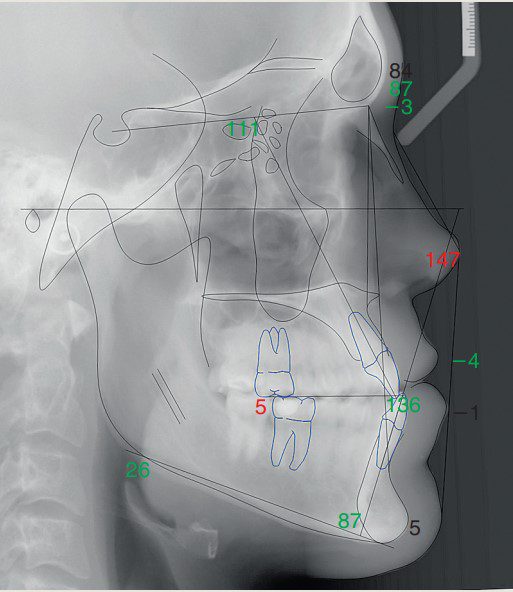

Tóm tắt phim sọ nghiêng (hình 2-16 và bảng 2-11 đến 2-14)

Tương quan xương hạng III với profile xương lõm, bao gồm:

- Xương hàm dưới nhô ra so với nền sọ

- Khớp cắn bù trừ với răng cửa hàm trên nghiêng ra trước và răng cửa hàm dưới nghiêng vào trong

- Chỉ số Wits loại III

- Profile mô mềm lõm

- Môi dưới nhô ra

- IMPA thấp hơn chuẩn 1,2 SD → răng cửa dưới hơi nghiêng vào trong.

- U1–Palatal plane cao hơn chuẩn 1,3 SD → răng cửa trên nghiêng ra trước.

- Góc liên răng cửa cao hơn chuẩn 1,1 SD → khớp cắn bù trừ (răng cửa trên nghiêng ra, răng cửa dưới nghiêng vào).

- Wits âm nhiều (–5,7 mm, lệch 4,7 SD) → đặc trưng của sai khớp cắn hạng III xương.